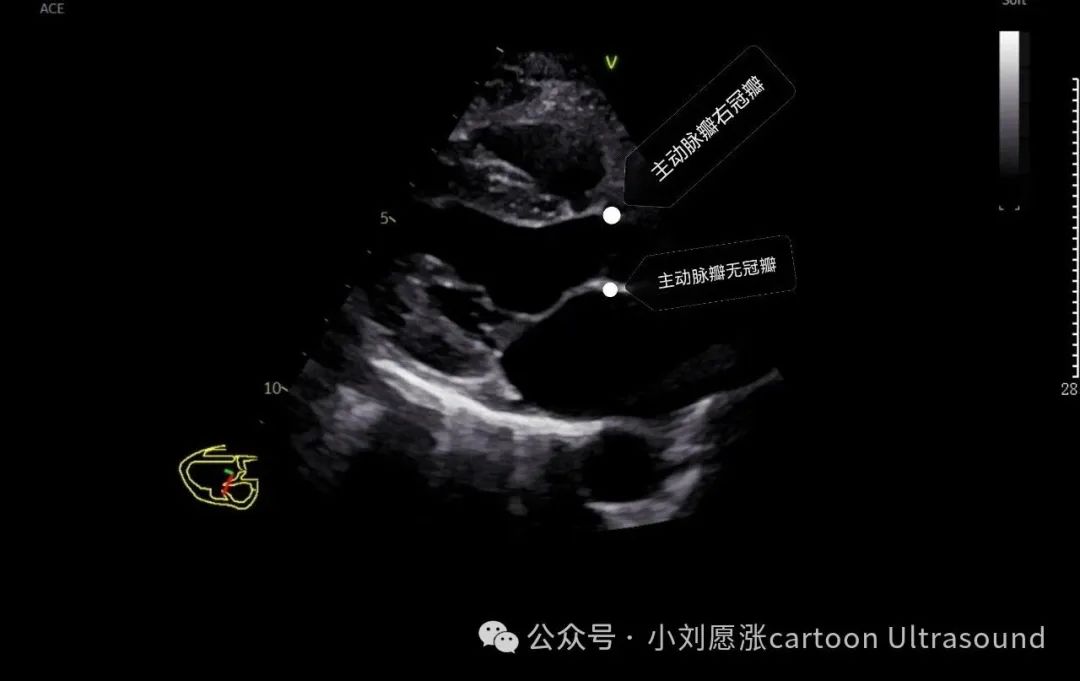

主动脉瓣:3个瓣叶,右冠瓣、左冠瓣、无冠瓣, 心底短暂切面 注意观察瓣叶个数,二叶是主动脉瓣畸形最多见。